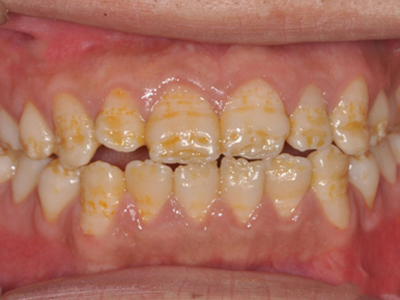

牙釉质发育不全牙表面上有坑图

牙釉质发育不全发展到严重时,导致牙釉质表面缺损,表现为带状、窝状的褐色凹坑,容易积存食物残渣诱发龋齿,表现为牙齿边上出现深褐色小洞。